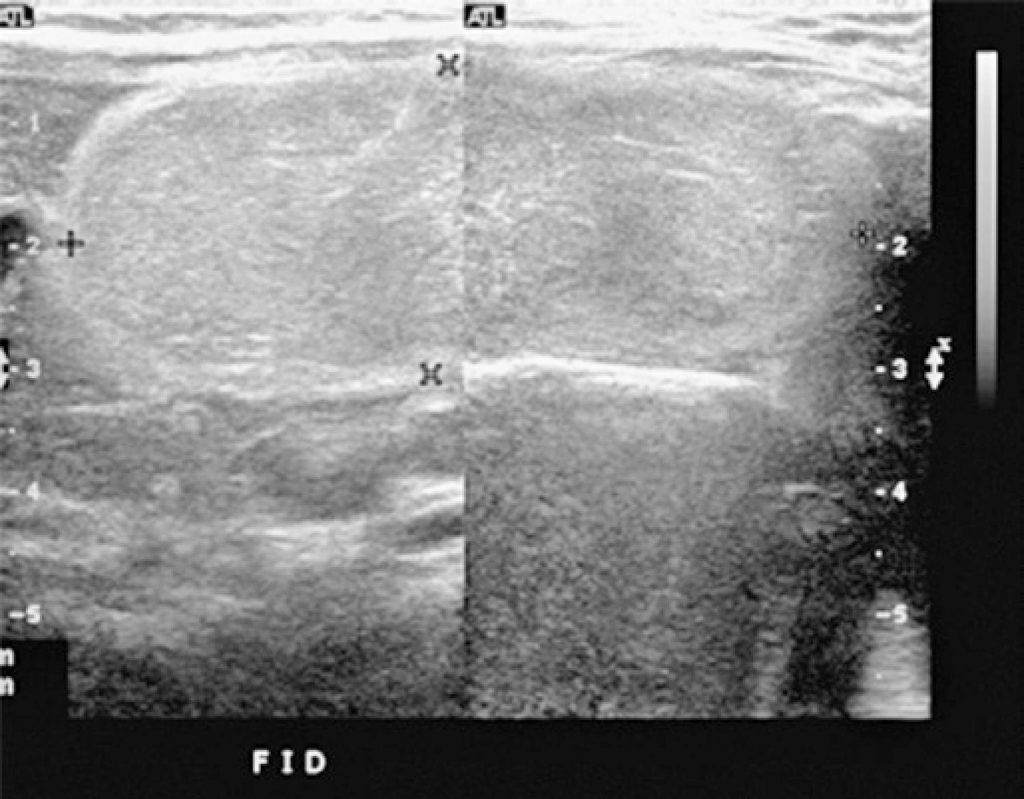

A 2-year-old female patient, admitted in the emergency room, presented diarrhea for 5 days and bloody stools in the last 24 hours. Physical examination revealed no significant findings. Ultrasound was initially performed, showing an elongated, well delimited and solid mass occupying since right hypocondrium until left iliac fossa, displacing adjacent structures. In sequence, magnetic resonance imaging was performed for confirmation of findings suggestive of omentum lipoma. After 1 week, the surgical resection was performed by videolaparoscopic acess. During 2-year follow-up, there was no sign of recurrence.